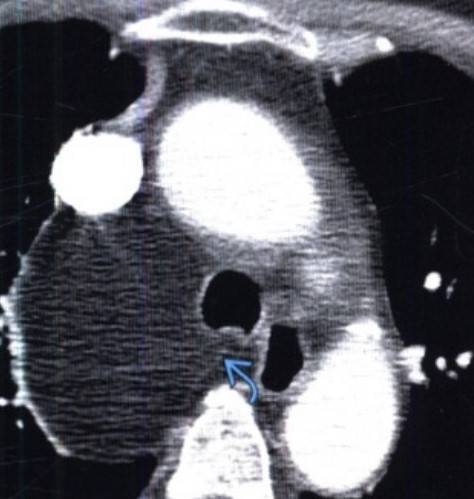

Признаки липомы средостения на КТ

Компьютерная томография с контрастным усилением (выявлено объемное образование с четким контуром, соответствующее жировой плотности, внутри визуализирована мягкотканная перегородка)

При проведении компьютерной томографии можно обнаружить опухоль и предположить характер патологического образования.

Критериями подозрения именно на липому являются:

- объемное образование;

- размер в большинстве случаев от 5 до 10 см, редко встречаются очаги большего диаметра;

- гомогенная консистенция;

- четкий контур;

- тонкие перегородки из соединительной ткани, толщиной около 2 мм;

- наиболее частое расположение – в переднем или периваскулярном отделе средостения;

- фиброзная капсула.

Рентгенолог изучает послойные снимки и на основании наличия/отсутствия перечисленных признаков формулирует заключение. Результат КТ не является окончательным диагнозом. Для абсолютно точного определения характера опухоли необходимо непосредственное изучение образующих неоплазию клеток. Материал для гистологического и цитологического исследования получают путем биопсии. Выбор места пункции должен осуществляться особенно тщательно из-за близости жизненно важных органов. Забор материала проводят под контролем КТ. Постановку заключительного диагноза и назначение соответствующего лечения осуществляет врач-онколог.